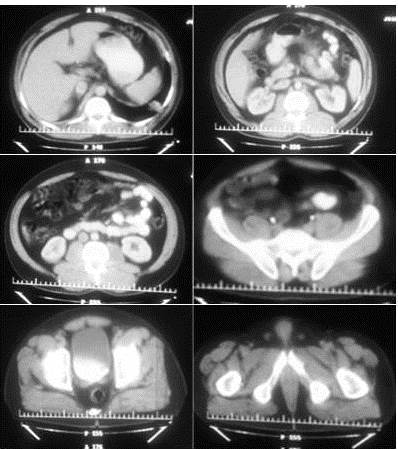

En vista del hallazgo radiológico y clínico, se procede a realizar TAC de tórax para completar el estudio de la paciente, con tomógrafo BRIGHT SPEED® de 16 detectores sin la administración de contraste intravenoso. Se evidencia imagen de masa con márgenes bien definidos con morfología redondeada, que mide entre 9 cm x 7 cm, con valores de atenuación entre 23-43 UH, isodensa homogénea, contornos suaves en contacto con pared torácica y sub-pleural. Ausencia de adenopatías de la cadena mediastinal, supra-carinalis y perihiliar (Figura 6).